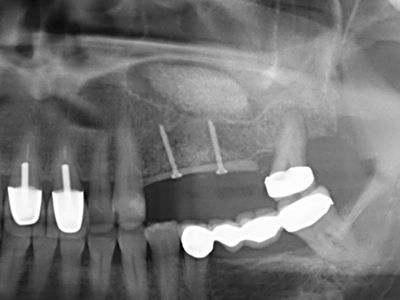

Piezo surgery has additional advantages when harvesting bone blocks. In addition to the high precision with osteotomy described above, the use of the thin saw tips specifically minimizes loss of material. Greater loss of material during harvesting can be expected with the thicker instrument tips, particularly when using Lindemann drills (Lakshmiganthan, Gokulanathan et al. 2012). The basal separation, which is necessary particularly for retromolar block transplants, is simplified by specially designed rectangular saws, with the result that piezo surgery is viewed as a precise, simple and safe procedure for harvesting retromolar bone blocks (Happe 2007) (Fig. 1-12).